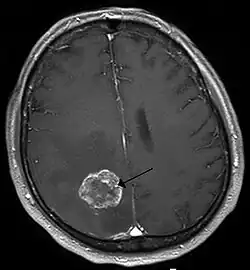

Glioblastom und andere primäre Hirntumoren

Das Wachstum eines Tumors ist schon in einer sehr frühen Phase von der Neubildung von Blutgefäßen (Neovaskularisation) begleitet, damit der Tumor ausreichend mit Sauerstoff und Nährstoffen versorgt werden kann. Bereits ab einem Durchmesser von 1 bis 2 mm beginnt die Neovaskularisation.[75] Die neugebildeten Blutgefäße weisen erhebliche strukturelle Unterschiede gegenüber den normalen Blutgefäßen auf. Bei Hirntumoren führen diese strukturellen Unterschiede zu signifikanten lokalen Veränderungen der Blut-Hirn-Schranke. Speziell beim Glioblastom ist die Neovaskularisation sehr stark ausgeprägt und mit ein Faktor für das aggressive Wachstum bei dieser Krebserkrankung.[76][14]

Die neugebildeten Blutgefäße primärer Hirntumoren weisen eine gewundenere Struktur als die normalen Blutgefäße des Gehirns auf. Die Endothelien sind von einer verformten Basallamina überzogen und exprimieren nicht mehr die Tight-Junction-Proteine Claudin-3 und Occludin.[77][78] Dem gegenüber wird in den Tumoren in großen Mengen der Vascular Endothelial Growth Factor (VEGF) produziert,[79][80] der die Endozytose des Zelladhäsionsproteins VE-Cadherin fördert und dadurch die Durchlässigkeit der Endothelien weiter erhöht.[81][14] Der Expressionsgrad von Occludin korreliert umgekehrt proportional mit dem Grading und der Durchlässigkeit der betroffenen Endothelien für Kontrastmittel, die eine gesunde Blut-Hirn-Schranke nicht passieren können.[78] Die erhöhte Permeabilität der Endothelzellen für bestimmte Kontrastmittel wird in der Diagnostik angewendet (siehe dazu den Absatz Humandiagnostik).

In der Therapie sind die Blutgefäße der Hirntumoren ein potenzielles Target für Angiogenese-Inhibitoren.[82][83][76] Die Zielstrukturen sind dabei unter anderem die αvβ3-Integrine (Cilengitide) und VEGF (Bevacizumab).